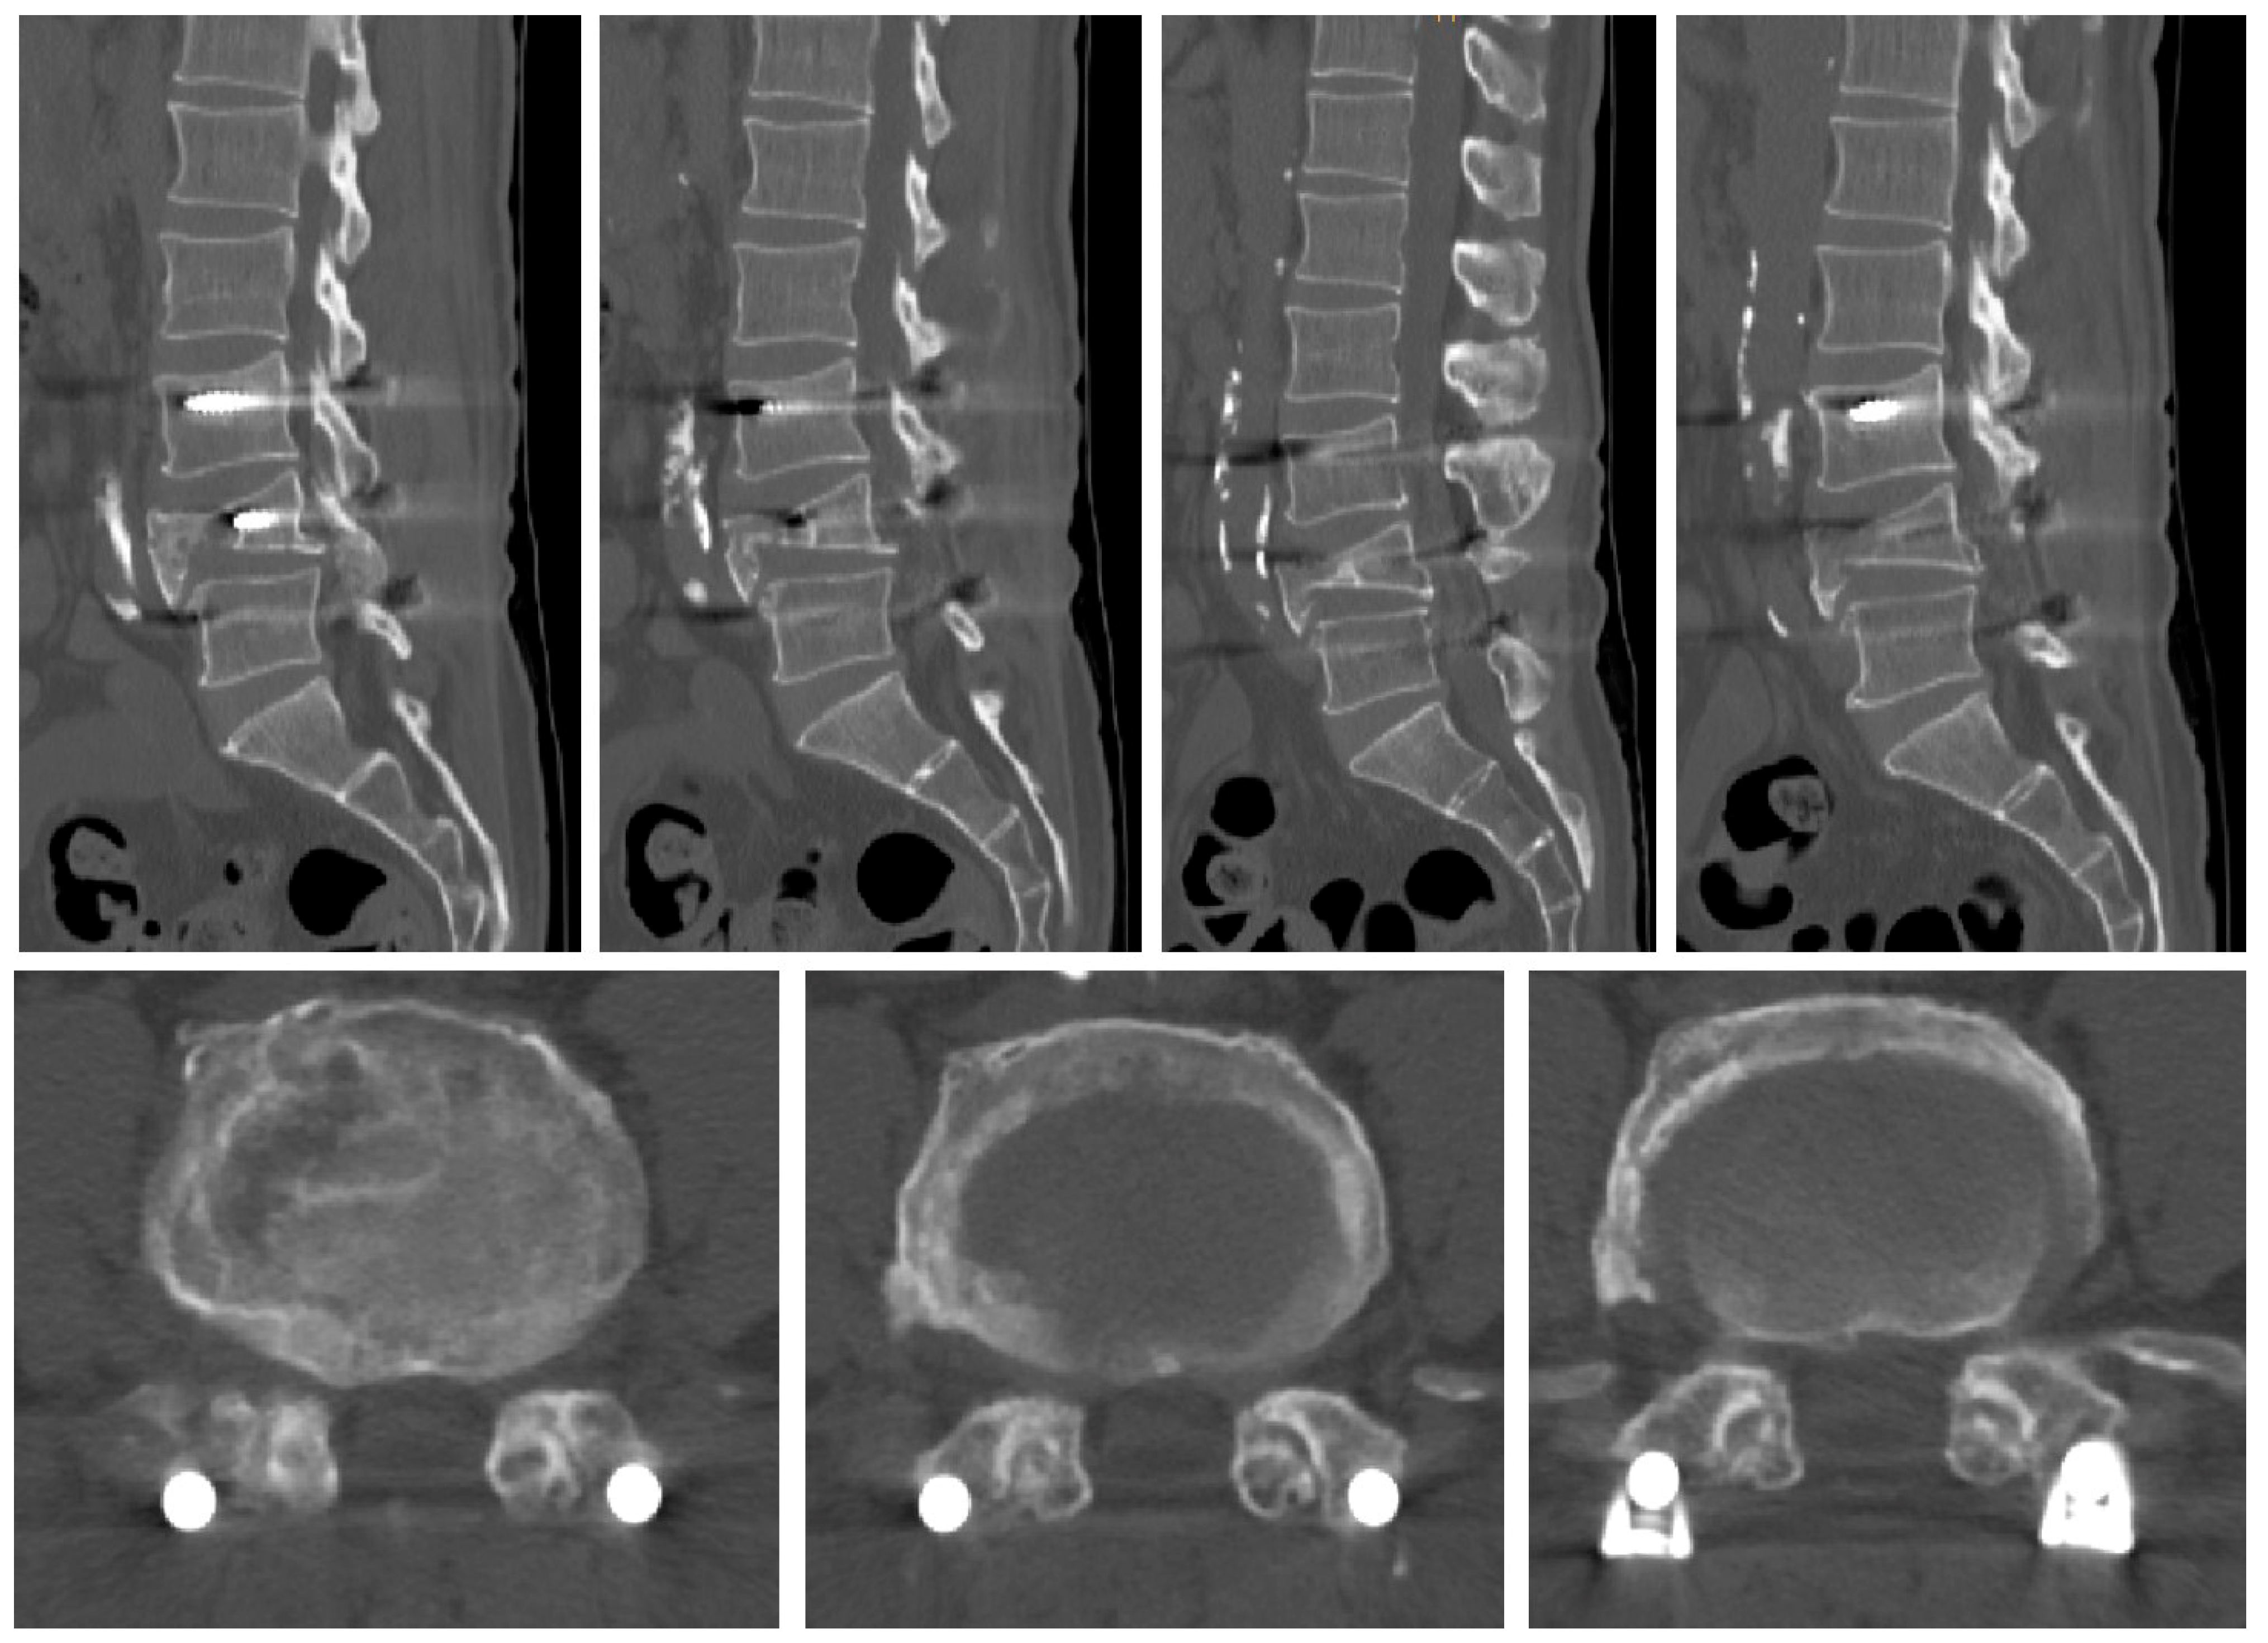

2.1. Case 1

2.2. Case 2